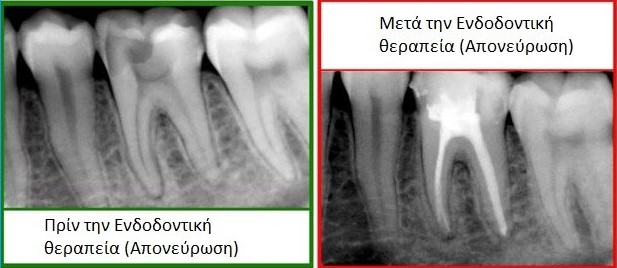

Πώς γίνεται η ενδοδοντική θεραπεία-απονεύρωση;

- Η απονεύρωση είναι μία διαδικασία που γίνεται για να αφαιρεθεί ο κατεστραμμένος ή νεκρός πολφός του ριζικού σωλήνα του δοντιού, μέσω του καθαρισμού του «άρρωστου» πολφού και στη συνέχεια της έμφραξης του ριζικού σωλήνα. Ο ριζικός σωλήνας γεμίζει με γουταπέρκα, ένα ελαστικό υλικό σαν καουτσούκ, για να προληφθεί η επανεμφάνιση μόλυνσης στο δόντι. Στη συνέχεια, το δόντι σφραγίζεται μόνιμα ή τοποθετούμε έναν άξονα και μία πορσελάνινη στεφάνη. Αυτό επιτρέπει στους ασθενείς να διατηρήσουν τα δόντια μέσα στην στοματική κοιλότητα για πάρα πολλά χρόνια.